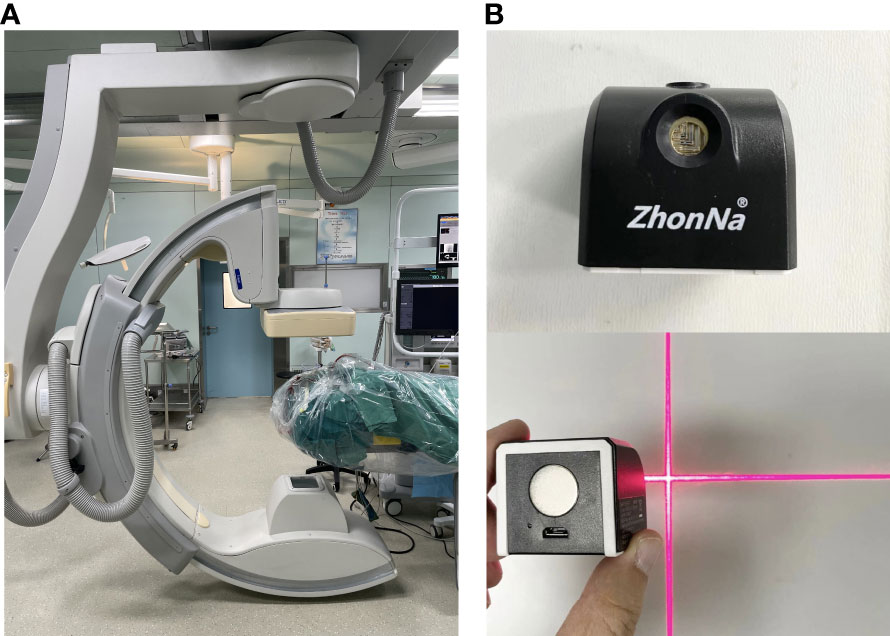

2.2 Experimental instrument

Instrumentation employed included Xper CT equipment (UNIQ FD20, made by Philips Medical Systems Nederland B.V.) and Laser locator (ZhonNa NX-9575-675, made by ZhonNa Electronics Company of Zhongshan) (Figure 1).